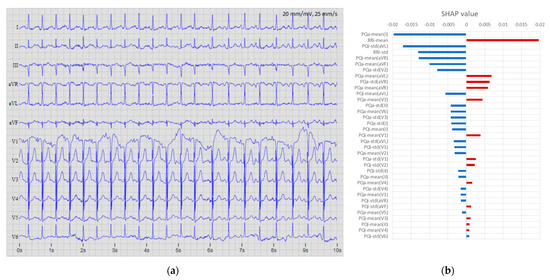

3.3. Test Feature Importance

- Lead-set importance (Figure 10b):

- Lead aVR is the most important lead due to three distinguished features: PQa-mean (61%), PQi-mean (43%), and PQa-std (26%).

- Lead I is the second most important lead due to the same three features as aVR: PQa-mean (51%), PQi-mean (26%), and PQa-std (26%).

- Lead aVL is ranked third for one feature: PQi-mean (50%).

- Leads V2, aVF, and II have one highlighted feature: PQi-std (43-55%).

- Lead V1 presents only one faintly distinguishable feature: PQa-std (28%).

- Leads III, V3, V4, V5, and V6 do not present any important features.

- Feature importance (Figure 10c):

- PQi-std is the most important feature mostly due to its high SHAP global metric in leads V2 (55%), aVF (52%), and II (43%).

- PQa-mean is the second most important feature, distinguished in leads aVR (61%), I (51%), and II (26%).

- PQi-mean is the third-ranked feature, distinguished in leads aVL (50%), aVR (43%), and I (26%).

- PQa-std is the least important feature, weakly emphasized in leads V1 (28%), I (26%), and aVR (26%).